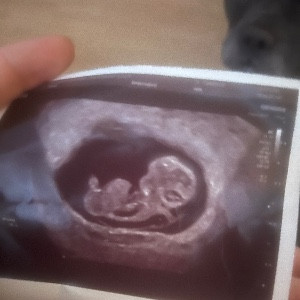

We're running 2k a day in January for families facing baby loss

We’ve committed to running 2k a day in January for every much-loved baby sadly not here today.

Sands ensure that everyone affected by the loss of a baby gets the support they need and deserve when facing the toughest of times. They campaign for change, provide training for midwives and healthcare professionals, and support research so that fewer babies die and so that less families experience the tragedy of losing their baby. Anything you are able to donate means so much.